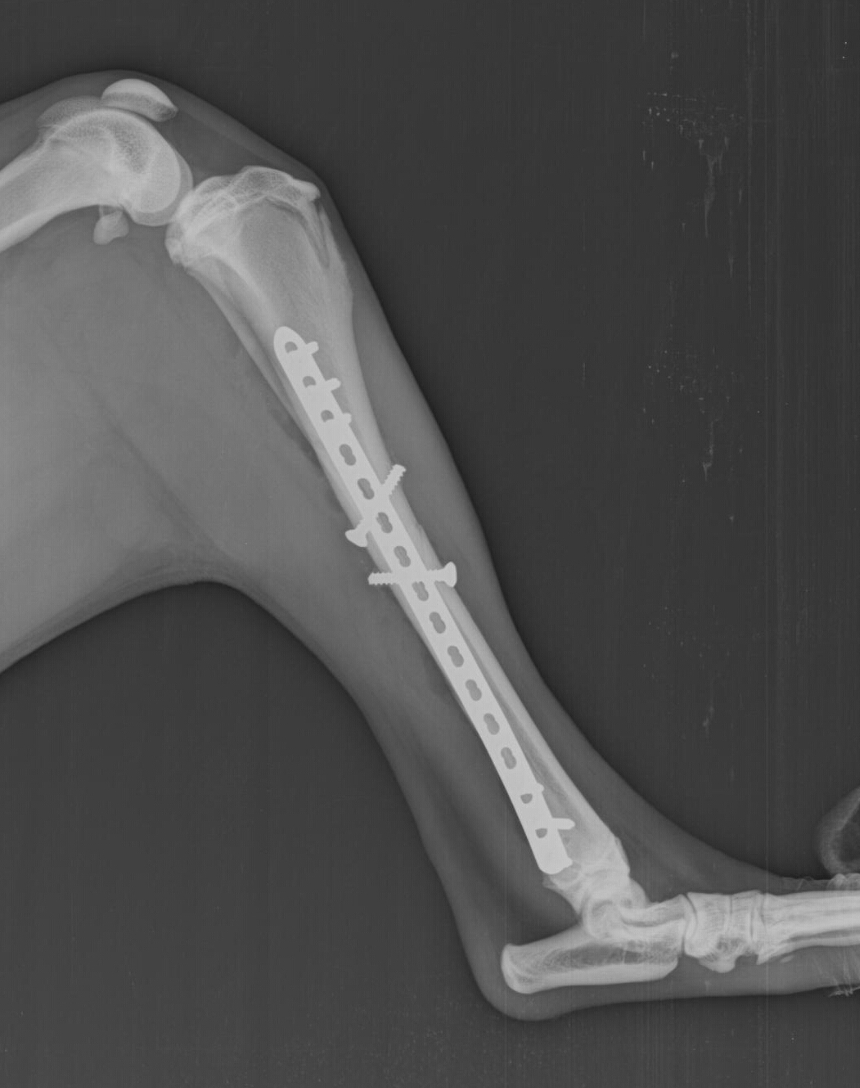

Frattura di lenta guarigione e che spesso lascia degli esiti importanti, trattata con fissatore esterno. L'epifisi prossimale presenta la faccetta per l'articolazione. Frattura biossea (tibia e perone) scomposta della gamba:

In questo caso, infatti, si dovrà ricorrere alla chirurgia per allineare le parti ossee. Frattura scomposta di tibia e perone della gamba destra. Cagliari, frattura scomposta per dessena: E' in relazione al grado di sofferenza e compromissione dei tessuti molli ed alla più o meno grave comminuzione dei capi di frattura della tibia ed buonasera dottore, il 12/07 ho subito un incidente in cui ho riportato la frattura scomposta ed esposta di tibia e perone sx. Frattura di tibia e perone. Come praticamente tutte le altre ossa del corpo umano, anche tibia e perone possono essere oggetto di frattura a seguito di traumi. Ancora oggi, a distanza di quasi 10. Elena è una giovane laureata in medicina, che mesi fa, ha avuto un brutto incidente procurandosi una frattura scomposta di tibia e perone. Prognosi delle fratture di tibia: Qual è la loro funzione? Contextual translation of rattura scomposta tibia e perone sinistri into english. Ridotta la frattura composta ed esposta di tibia e perone. Presenta un'epifisi prossimale, un corpo con tre facce delimitate da altrettanti margini ed un'epifisi distale. Cosa sono tibia e perone? Quando si frattura un osso, esso può rimanere confinato nella cute integra (fratture chiuse) oppure… nel caso di frattura composta, la difficoltà del trattamento da parte del medico è senz'altro minore, mentre nel caso di frattura scomposta è necessaria una manipolazione. Frattura esposta nel wrestling , caduta dall alto con frattura esposta alla gamba. La frattura della tibia e del perone consiste in una lesione potenzialmente grave, in quanto non viene danneggiato soltanto l'osso ma anche i tessuti molli circostanti, muscoli, vasi sanguigni, tendini, legamenti e cute.